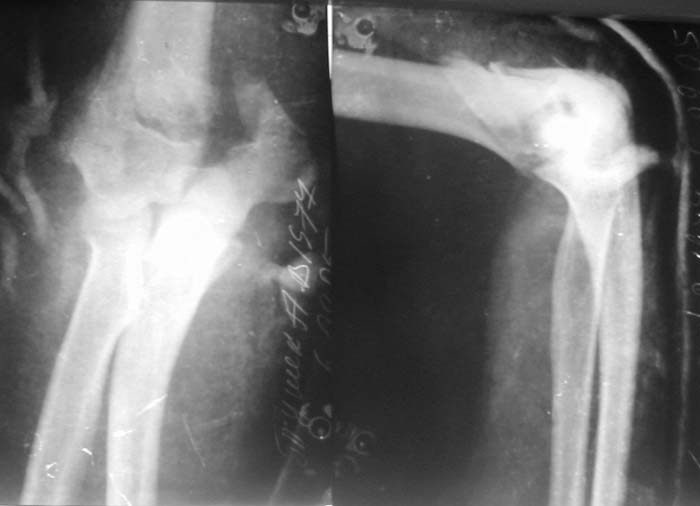

Солидарен с мнением обоих Александров (Челнокова и Рыкова): точную репозицию такого перелома вряд ли удастся выполнить закрыто. Даже во время открытого вмешательства это сделать непросто. Неслучайно предложен костно-пластический доступ с временным отсечением локтевого отростка. И по методу фиксации согласен с Александром Челноковым: 2 пластины. В качестве примера привожу рентгенограммы одного из наших пациентов с аналогичным повреждением.

С уважением, А. Золотов, Приморский край.